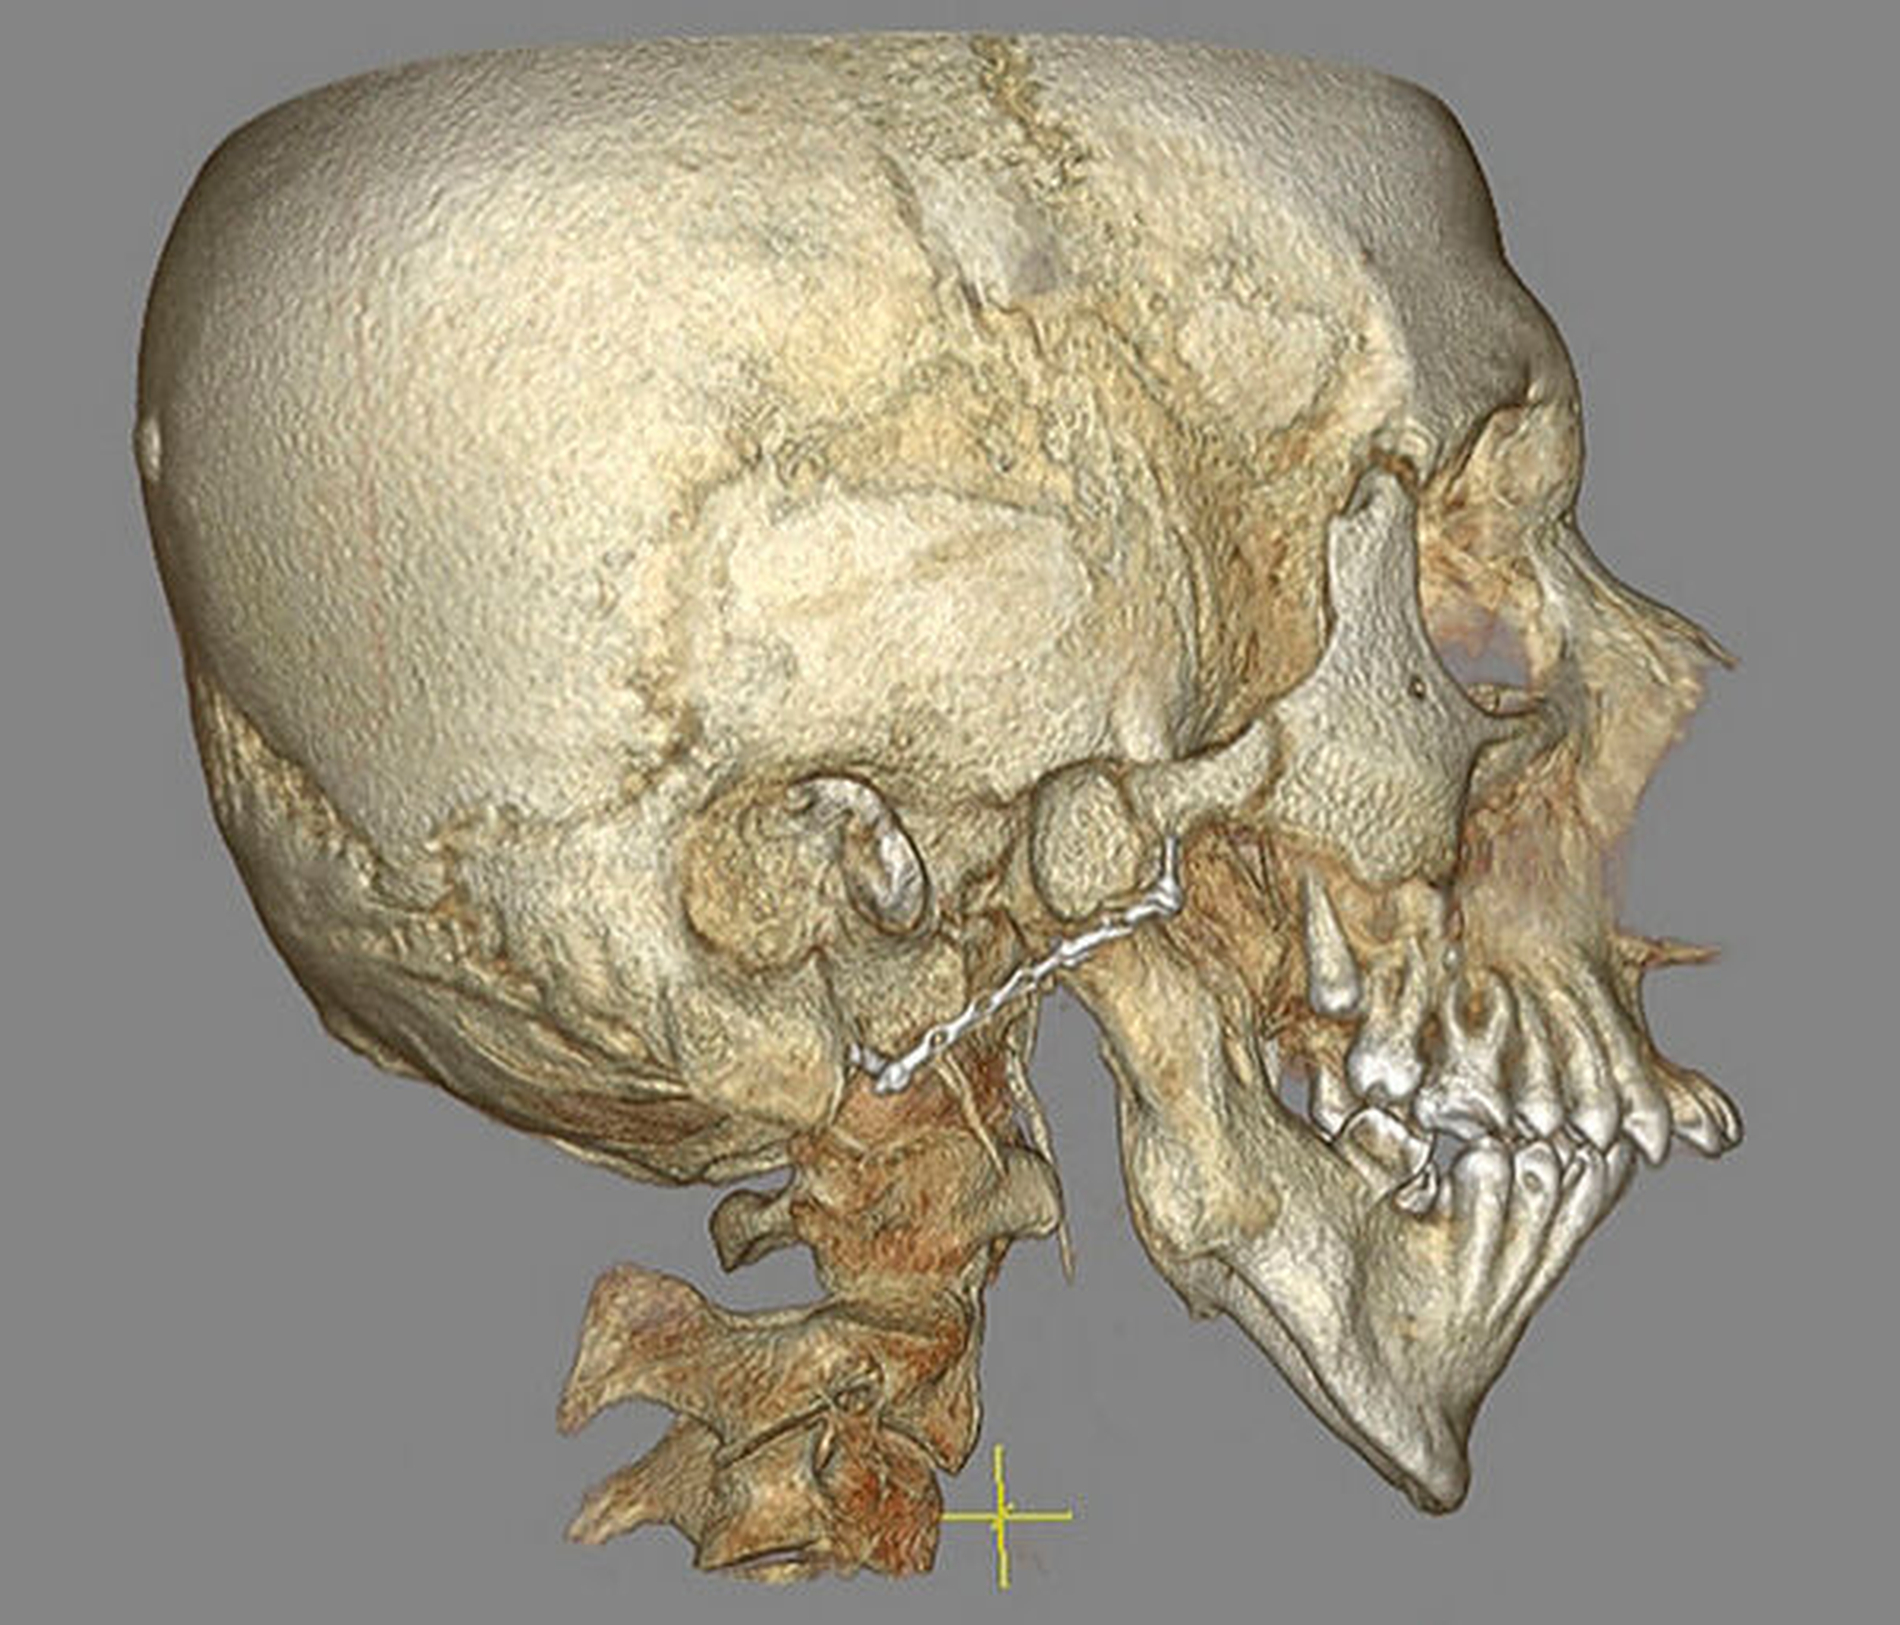

Aus der Krankengeschichte des Patienten ergab sich eine im Jahr 2009 durchgeführte Operation mit costochondralem Kiefergelenksersatz rechts aufgrund einer fortgeschrittenen Kiefergelenksarthrose infolge eines Sturzereignisses mit beidseitig unbehandelter Collumfraktur im Kindesalter. Eine noch am Tag der Erstvorstellung durchgeführte DVT-Untersuchung zur Beurteilung der Kiefergelenke bei ausgeprägter Unterkieferhypomobilität bestätigte die Verdachtsdiagnose einer Kiefergelenksankylose Typ IV rechts und Typ III links nach Sawhney [Sawhney, 1986] beziehungsweise Wilkes Typ V [Wilkes, 1989] beidseits (Abbildung 2).